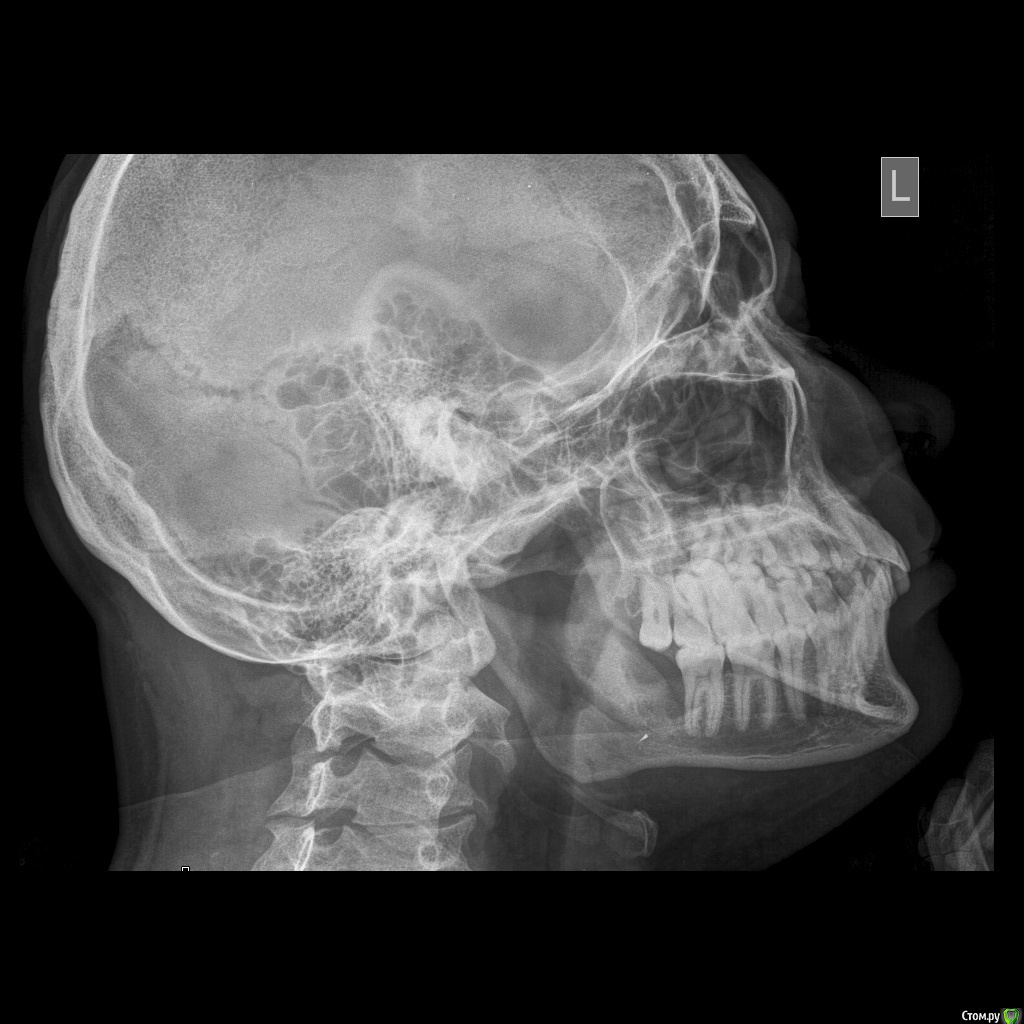

medbratec Опубликовано 10 октября, 2016 Автор Поделиться Опубликовано 10 октября, 2016 Хорошо, что напомнили есть у меня и оптг, правда этот снимок делал через неделю после операции. Есть смысл обновить или делать тогда уже клкт ?Действительно, на нем есть этот осколок, а я не обратил внимание сразу, да и доктор ничего не сказал, умышлено ли ?Цефтриаксон в этом году уже два раза колол, цифран в таблетках перед операцией, может Цефотаксим, но это уже забегаю вперед.Можете посоветовать специалиста в Крыму ?http://i.piccy.info/i9/94fbc0ec797e8c426985282fd6ba0a17/1476107444/5676/1073892/Novozhylov_V_A_240.jpghttp://i.piccy.info/a3/2016-10-10-13-50/i9-10379003/240x118-r/i.gif Ссылка на комментарий

kriokov Опубликовано 10 октября, 2016 Поделиться Опубликовано 10 октября, 2016 на оптг следы контраста от йодоформного тампона, не видно четко кортикальную, да и время прошло. Лучше клкт. Крымских стоматологов не знаю к сожалению 1 Ссылка на комментарий

medbratec Опубликовано 12 октября, 2016 Автор Поделиться Опубликовано 12 октября, 2016 Был на консультации в частной клинике.Вердикт - семерку лучше пока не трогать, ее чувствительность обусловлена оголенными корнями. Проводить ревизию лунки, доставать осколок вежливо отказались, и отправляют с этим в челюстно-лицевую.Посоветовали сделать клкт для прояснения картины. Я сделал, однако повторную консультацию пришлось отложить. Не знаю как оттуда вытащить картинки. Если кому будет не лень, то оставлю ссылку на скачивание образа диска. (600мб)Рентгенолог сказал, что осколок в мягких тканях, причем с внутренней стороны, также обнаружилась кариозная полость в месте соприкосновения 7-го и 6-го зуба. Ссылка на комментарий

medbratec Опубликовано 13 октября, 2016 Автор Поделиться Опубликовано 13 октября, 2016 Я вас прекрасно понимаю. Был бы специалистом, то так сразу и сделал. Просто не знаю, что конкретно и под каким углом показывать. Сделал несколько скриншотов. Напишите, если они окажутся не слишком информативны. Ссылка на комментарий